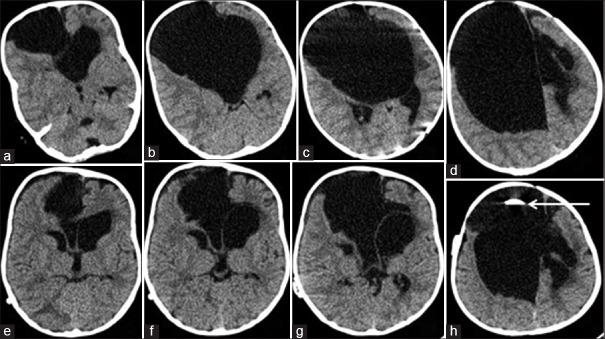

Figure 1.

Preoperative axial computed tomography scan (a-d) of a 9-month-old child with a large frontal interhemispheric arachnoid cyst (Barkovich Type 2a) with agenesis of corpus callosum. He underwent right frontal medium pressure cystoperitoneal shunt. Postoperative day 1, axial computed tomography scan (e-h) a significant resolution of cyst volume and hydrocephalus (arrow indicates the catheter inside the cyst)